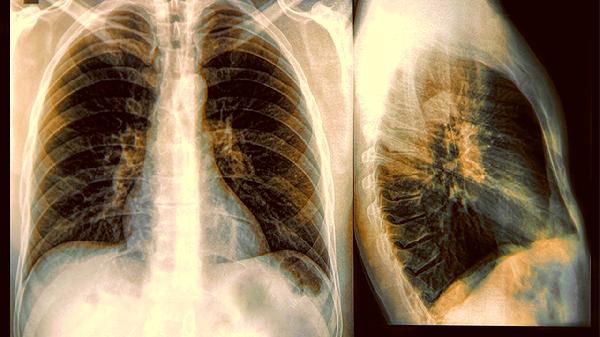

即使症狀緩解,支原體感染可能需要復查胸片確認肺部情況。流感痊癒後如果又出現發熱或咳嗽加重,要警惕繼發細菌感染的可能。